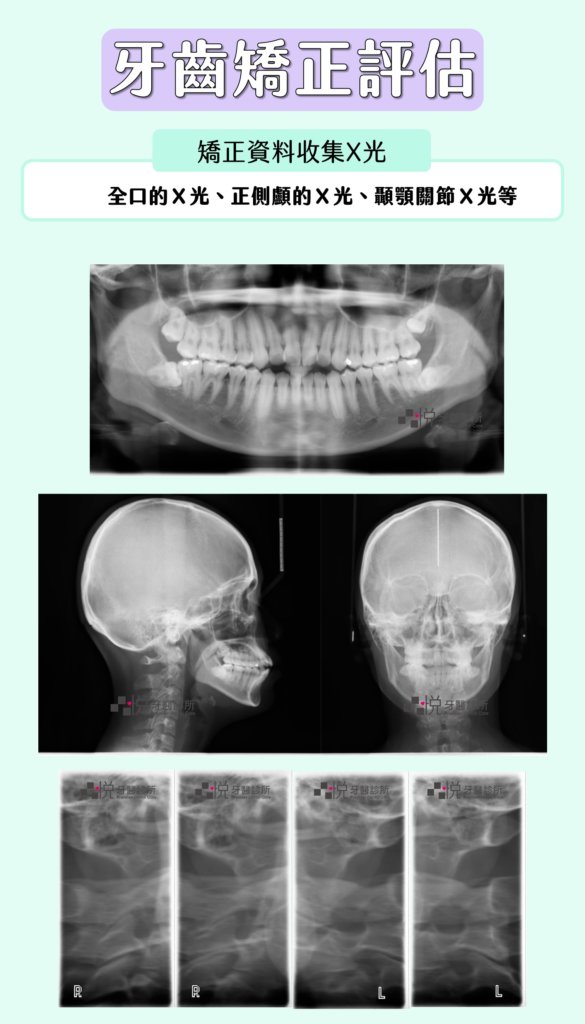

矯正牙齒

牙齒矯正前的資料收集,會拍攝多種類型的X光片,包含全口的X光、正側顱的X光、顳顎關節X光等,讓矯正醫師有充足的數據分析,進而擬定合適的矯正計畫。

矯正資料收集的X光包含:全口的X光、正側顱的X光、顳顎關節X光。

在牙齒矯正期間,通常醫師會於矯正的每半年會再拍攝全口的X光片,以檢查肉眼所看不到的牙根的移動狀態,並同步檢查是否有蛀牙或安排家庭牙科醫師進行洗牙。